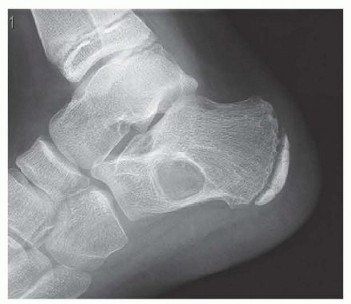

Operative Management of Unicameral Bone Cyst, Aneurysmal Bone Cyst, and Nonossifying Fibroma UNICAMERAL BONE …